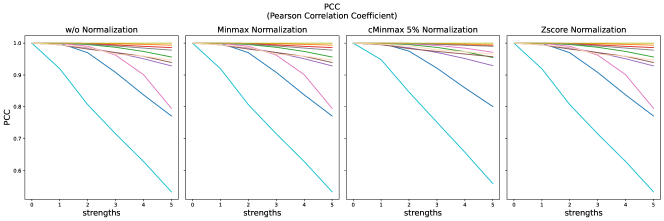

The results for all strengths are given in Figs. A.1-A.4. In Tab. 5 - 8, the results for distortions of maximal strength (s=5) are summarized.

For all applied distortions, all reference metric scores monotonously measure lower similarity for increasing distortion strengths.

Without applying any normalization, all metrics beside NMI are very sensitive to intensity shifts (see Tab. 5). However, with any normalization method, intensity shifts are fully compensated, and all metrics measure perfect similarity.

Across all normalization methods, all metrics are very sensitive to translation and not very sensitive to replace artifacts.

SSIM similarity scores for strong blurring are very high, compared to most other distortions.

Gaussian noise is better detected with Minmax normalization, while stripe artifacts seem to be less detected with Zscore normalization.

PSNR scores generally display only very small changes for strengths larger than 2 (see Fig. A.1). PSNR values are higher for Zscore normalization.

Images distorted with Gaussian blurring and ghosting artifacts receive very high PSNR similarity scores, especially with small distortion strengths.